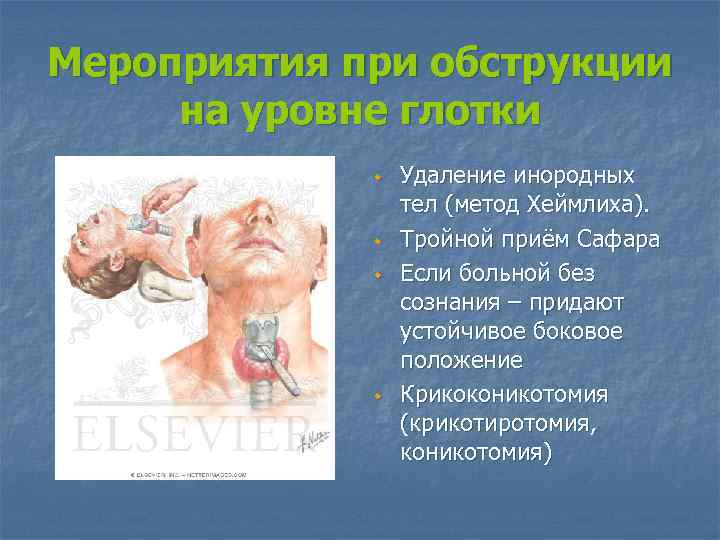

Мероприятия при обструкции на уровне глотки w w Удаление инородных тел (метод Хеймлиха). Тройной приём Сафара Если больной без сознания – придают устойчивое боковое положение Крикоконикотомия (крикотиротомия, коникотомия)